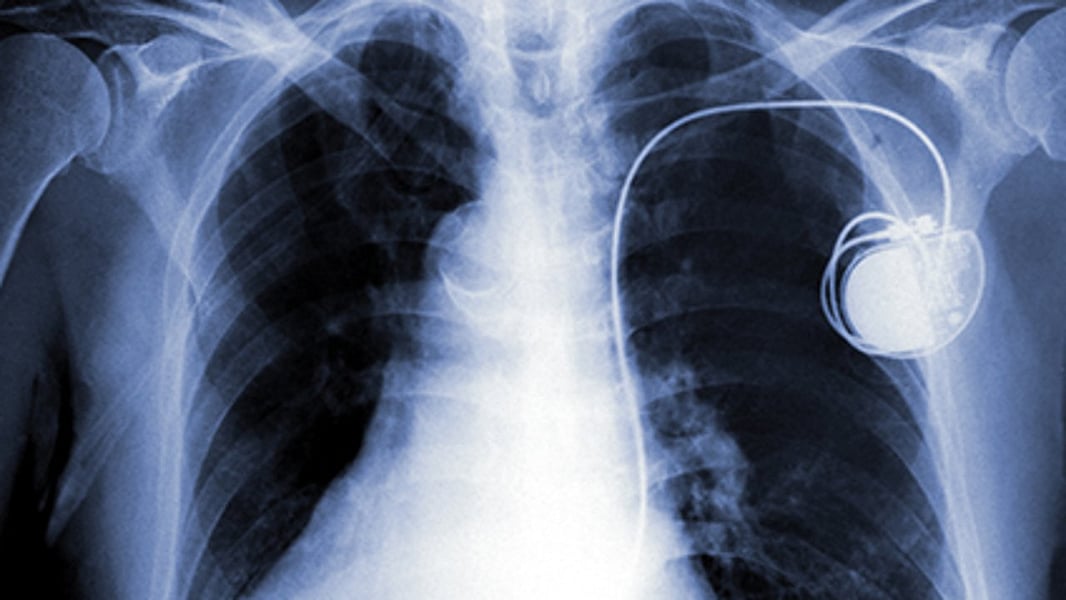

Does A Smartwatch Interfere With A Pacemaker . Do smartwatches stop pacemakers and icds from working properly? Apple has listed products it says should be kept a safe distance away from medical devices like pacemakers and. However, it is important to consult with your doctor before. Recent research has raised questions about whether certain types of smart gadgets can interfere with pacemakers and implantable defibrillators, potentially leading to pacing interruptions or unnecessary shocks. Researchers say there is a possibility that fitness trackers on smartphones can interfere with the workings of implanted devices such as pacemakers. Pacemakers are sensitive to electrical equipment that emits a strong electromagnetic field like an induction hob, or. Yes, it is generally safe to wear a smartwatch with a pacemaker. Smart watches and other consumer devices should be kept at least 6 inches away from a pacemaker.

Do smartwatches stop pacemakers and icds from working properly? Apple has listed products it says should be kept a safe distance away from medical devices like pacemakers and. Pacemakers are sensitive to electrical equipment that emits a strong electromagnetic field like an induction hob, or. Smart watches and other consumer devices should be kept at least 6 inches away from a pacemaker. Recent research has raised questions about whether certain types of smart gadgets can interfere with pacemakers and implantable defibrillators, potentially leading to pacing interruptions or unnecessary shocks. Researchers say there is a possibility that fitness trackers on smartphones can interfere with the workings of implanted devices such as pacemakers. Yes, it is generally safe to wear a smartwatch with a pacemaker. However, it is important to consult with your doctor before.